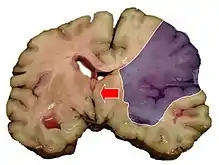

Midline shift is a shift of the brain past its center line.[1] The sign may be evident on neuroimaging such as CT scanning.[1] The sign is considered ominous because it is commonly associated with a distortion of the brain stem that can cause serious dysfunction evidenced by abnormal posturing and failure of the pupils to constrict in response to light.[1] Midline shift is often associated with high intracranial pressure (ICP), which can be deadly.[1] In fact, midline shift is a measure of ICP; presence of the former is an indication of the latter.[2] Presence of midline shift is an indication for neurosurgeons to take measures to monitor and control ICP.[1] Immediate surgery may be indicated when there is a midline shift of over 5 mm.[3][4] The sign can be caused by conditions including traumatic brain injury,[1] stroke, hematoma, or birth deformity that leads to a raised intracranial pressure.

Three main structures are commonly investigated when measuring midline shift. The most important of these is the septum pellucidum, which is a thin and linear layer of tissue located between the right and left ventricles.[7] It is easily found on CT or MRI images due to its unique hypodensity.[7] The other two important structures of the midline include the third ventricle and the pineal gland, which are both centrally located and caudal to the septum pellucidum.[6][7] Identifying the location of these structures on a damaged brain compared to an unaffected brain is another way of categorizing the severity of the midline shift. The terms mild, moderate, and severe are associated with the extent of increasing damage.

Midline shift measurements and imaging has multiple applications. The severity of brain damage is determined by the magnitude of the change in symmetry. Another use is secondary screening to determine deviations in brain trauma at different times after a traumatic injury as well as initial shifts immediately after.[3] The severity of shift is directly proportional to the likeliness of surgery having to be performed. The degree of MLS can also be used to diagnose the pathology that caused it. The MLS measurement can be used to successfully distinguish between a variety of intracranial conditions including acute subdural hematoma,[5][7] malignant middle cerebral artery infarction,[3] epidural hematoma, subarachnoid hemorrhage, chronic subdural hematoma, infarction, intraventrical hemorrhage, a combination of these symptoms, or the absence of pertinent damage altogether.[7]